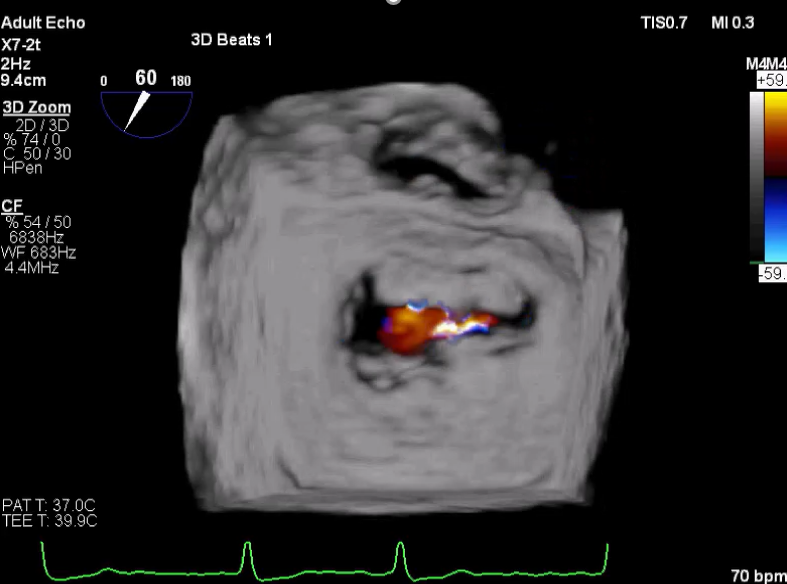

术中超声

3D视图打开夹子

3D视图下观察二尖瓣双孔形态

3D-color:残余少量返流